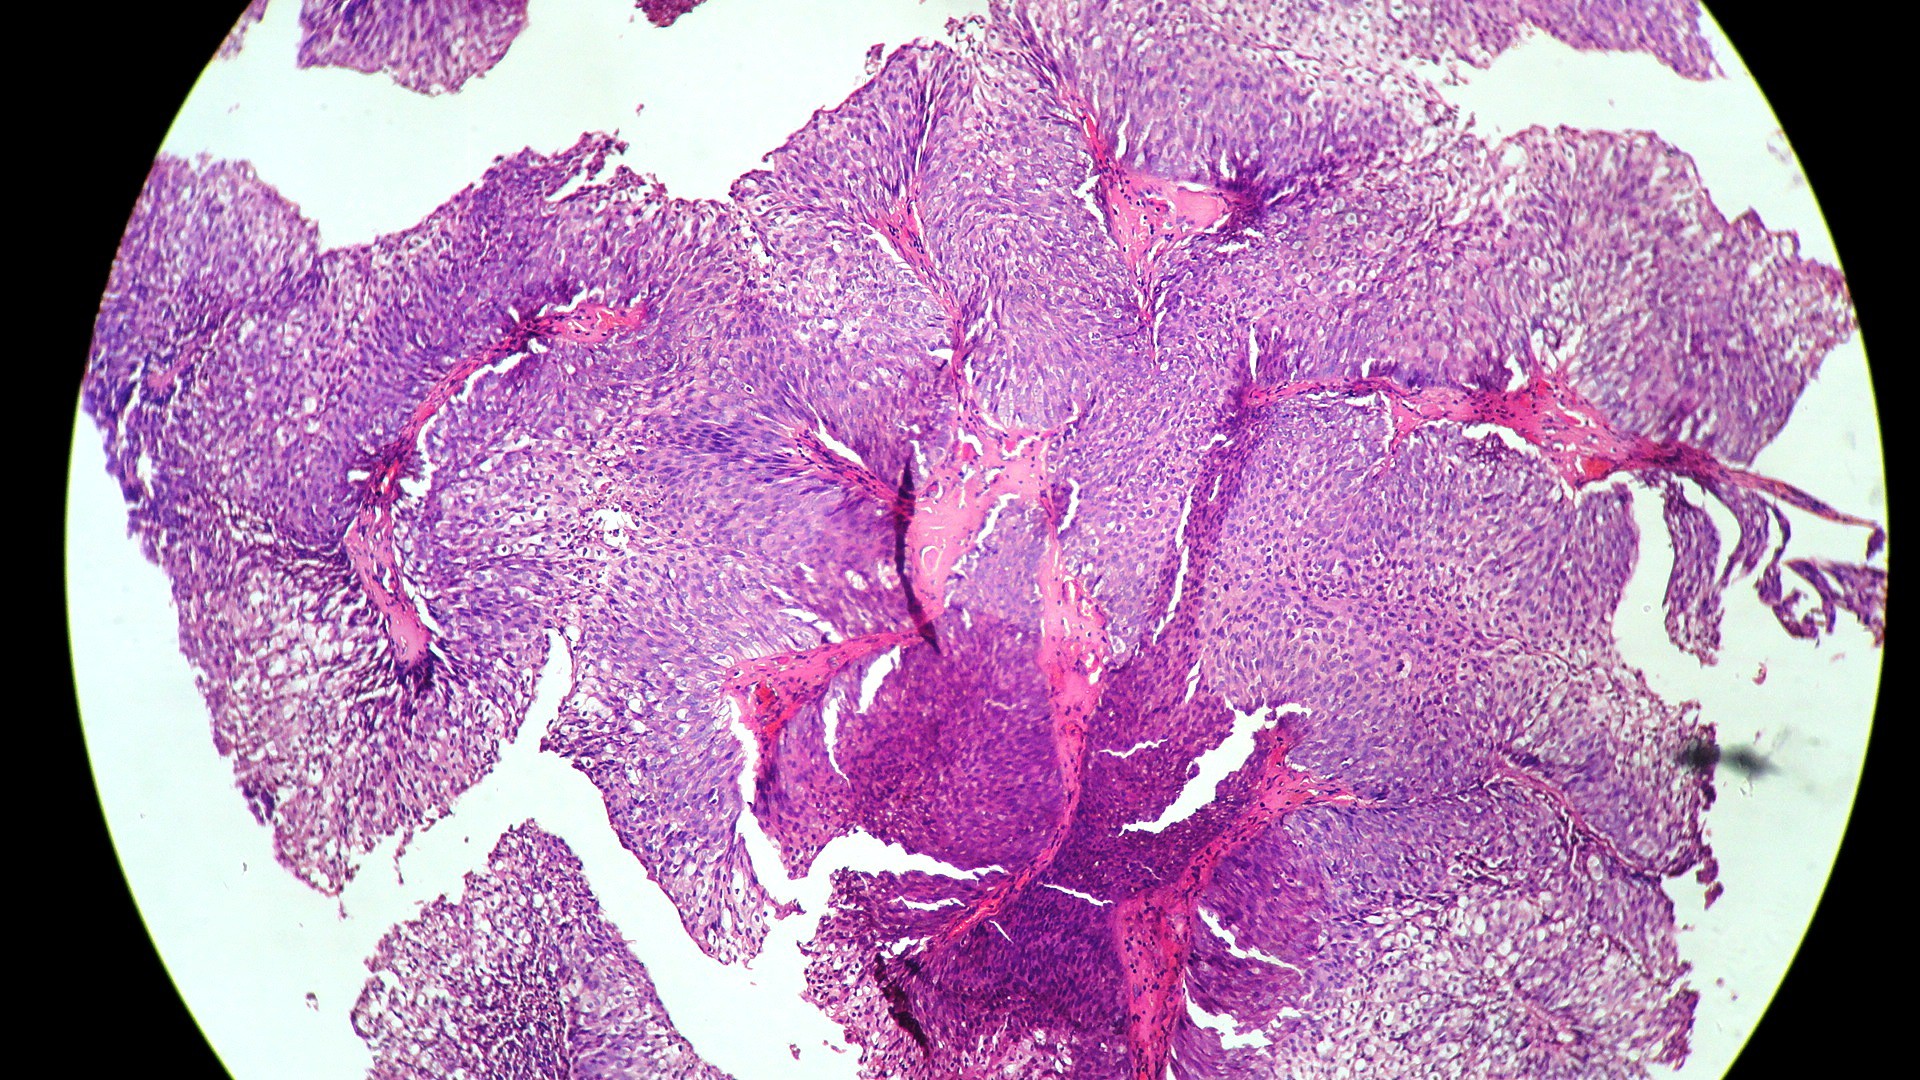

In our study, we made an attempt to evaluate the pattern of tumor growth, its degree of differentiation, progression and associated mucosal changes. In 15 cases of urothelial papilloma, it is characterized by discrete papillary growth with a central fibrovasular core lined by urothelium of normal thickness and cytology (Figure 1). In five cases of Papillary urothelial neoplasm of low grade malignant potential (PUNLMP), histopathologically the tumor is characterized by delicate, orderly, tenuous papillary structures with orderly arrangement of cells within the papillae with minimal architectural abnormalities and nuclear atypia usually limited to basal layer irrespective of cell thickness (Figure 2). The major distinction from papilloma is that in PUNLMP the urothelium is much thicker and nuclei are significantly enlarged. In 21 cases of low grade urothelial carcinoma, histologically it is characterized with papillary axes which are more compact, crowded, fused at the base and lined by unordered cells showing both architectural and cytological abnormalities with frequent mitosis (Figure 3). In 51 cases of high grade urothelial carcinoma showed fused papillary axes over the large areas resulting in sheets and solid areas. The cells have enlarged, hyperchromatic, pleomorphic nucleus in full thickness of the epithelium with increased atypical mitosis (Figure 4). As per TNM staging used in our study we observed majority of the bladder tumours were invasive accounting for 78.25% (Figure 5 & 6) as compared to non-invasive bladder tumours constituting 21.73% of the cases as shown in table 3.